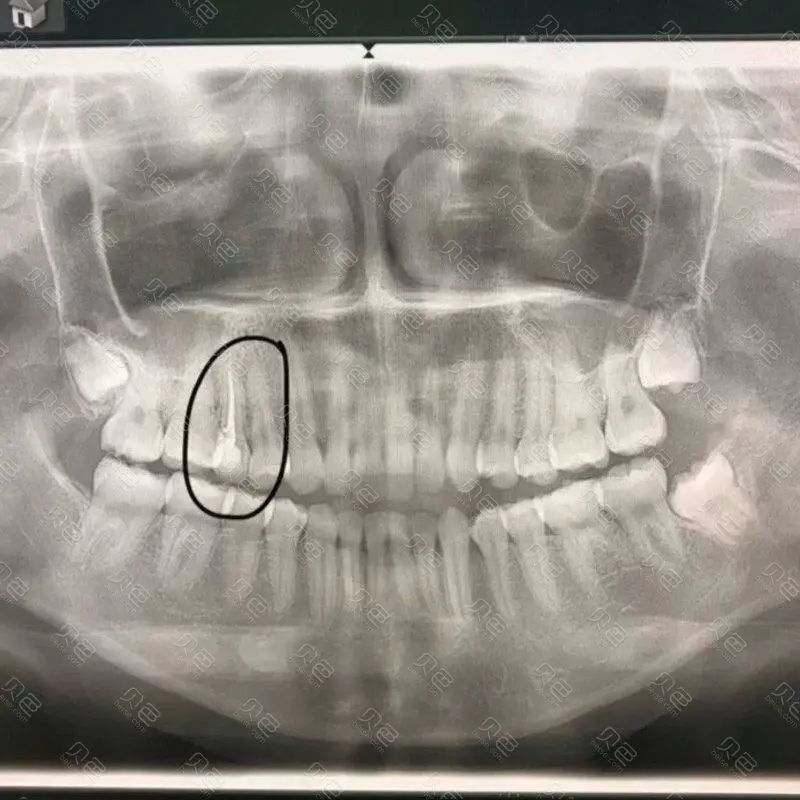

举个例子,下图这位大叔已经年过六旬了,大家可以注意到他的牙片。

曲面断层片怎么看科普知识:你会看牙片嘛?今天手把手教你看!_https://www.jmylbn.com_新闻资讯_第10张